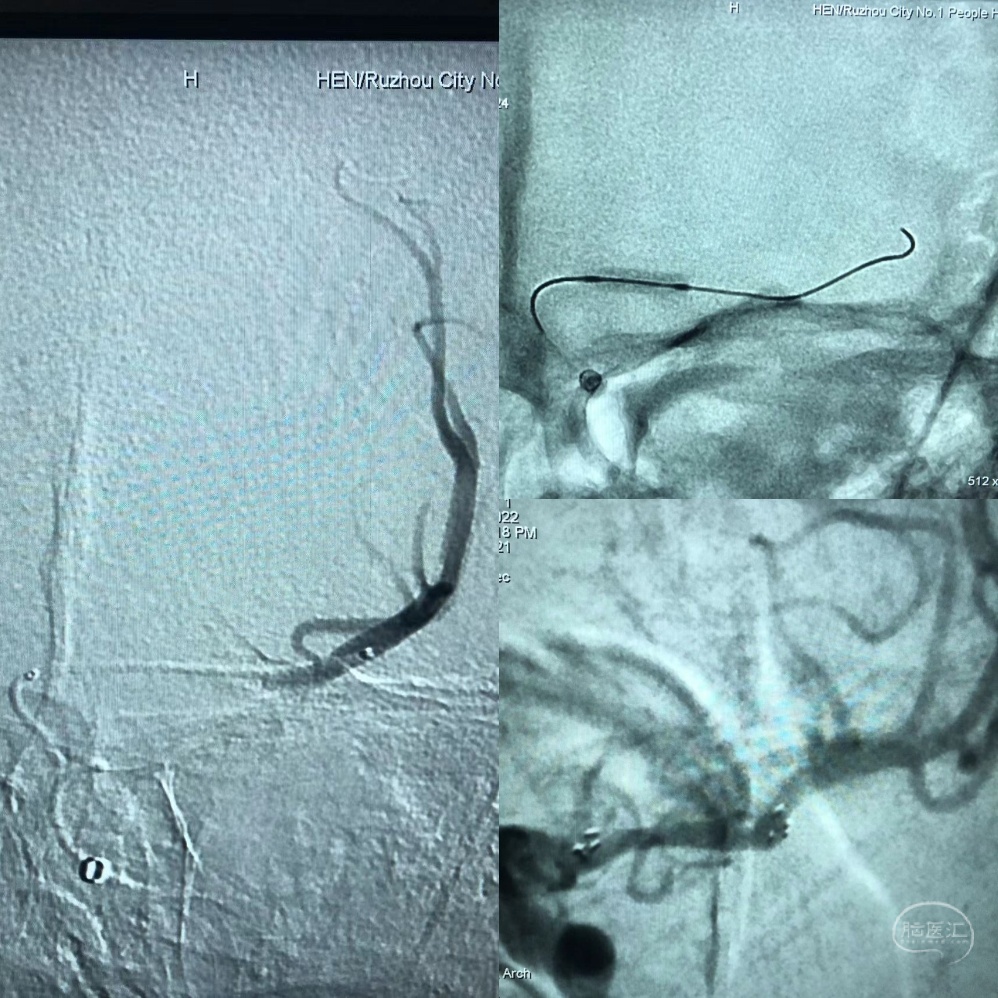

8FGuilding+6F115Navien建立通路。

Synchro200mm微导丝配合Rebar18微导管穿越闭塞段,经Navien及微导管造影提示闭塞段位于左侧大脑中动脉中段,闭塞段很短,推测血栓负荷量极少。

送入300mmSynchro微导丝,Gateway2.5*9mm球囊扩张后,观察血流,出现弹性回缩。再次扩张后,撤出球囊,交换PLUS导管,送入Enterprise4.0*23mm支架,顺利释放,血流维持可,轻度残余狭窄。

术后造影,血流通畅,TICI分级3级。